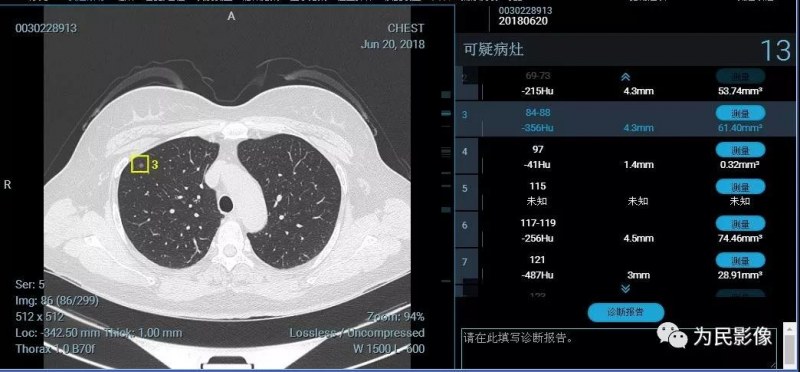

在肺結(jié)節(jié)篩查中,人工智能更多充當(dāng)醫(yī)生的第二雙眼睛。我們都知道,高分辨CT包含幾百幅圖像,人眼識(shí)別很容易漏診。AI軟件可以很快幫助醫(yī)生發(fā)現(xiàn)結(jié)節(jié),并檢測(cè)結(jié)節(jié)相關(guān)信息—密度、大小等,進(jìn)而醫(yī)生可以通過(guò)相關(guān)特點(diǎn)進(jìn)行判斷,防止醫(yī)生漏診并明顯提高工作效率。

(以上兩例患者憑醫(yī)生肉眼很容易漏診,人工智能發(fā)現(xiàn)的微結(jié)節(jié)均需要隨診復(fù)查。)